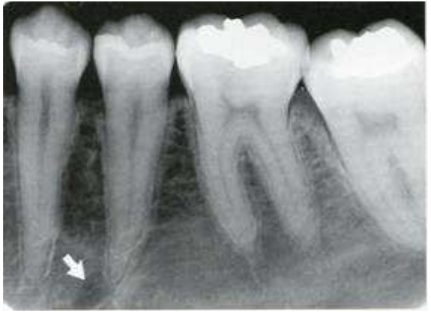

66.下圖中白色箭頭所指位於左下顎第二小臼齒根尖部位之放射線透過性(radiolucent)影像, 根據X光片影像中資訊判斷,下列何者最有可能?

(A)Apical granuloma (B)Radicular cyst (C)Dentoalveolar abscess (D)Mental foramen